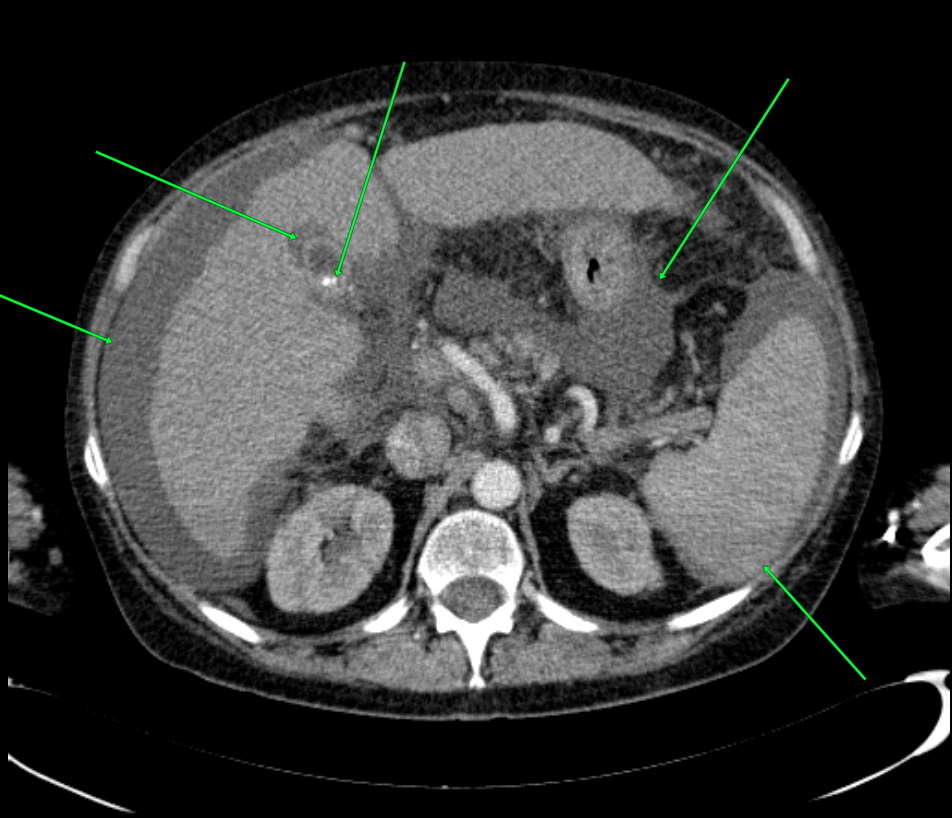

КТ диагностика тубоовариального абсцесса: Подходы и изображения

Раздел: Объективный взгляд